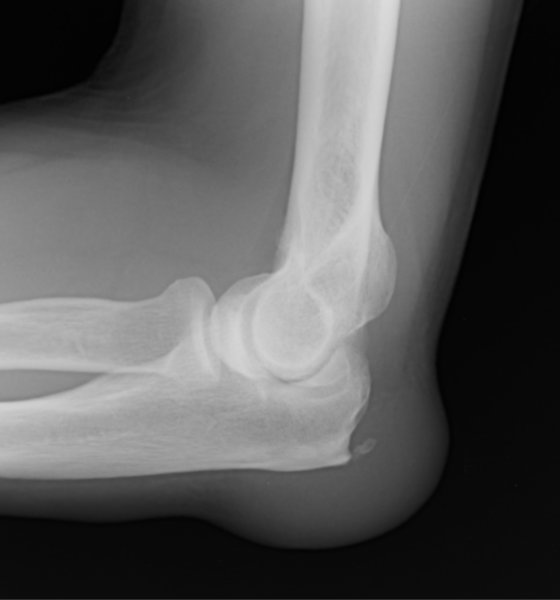

Common Superficial Bursitis AAFP